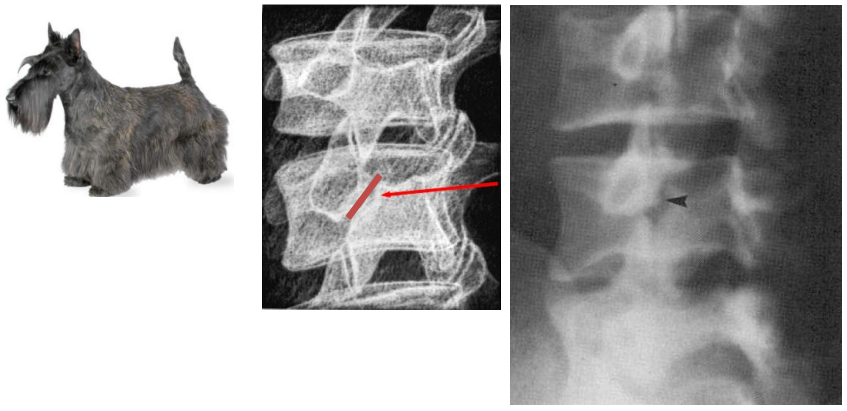

• Na avaliação radiográfica, o que representa o cachorro de Lachapelle na espondilolistese ístimica?

A

• Visualizado na incidência oblíqua

• Articulação superior → orelha

• Pescoço → pars (fratura = coleira)

• Olho → pedículo

• Focinho → processo transverso

• Processos articulares inferiores → patas

• Corpo → lâmina e processo espinhoso

23